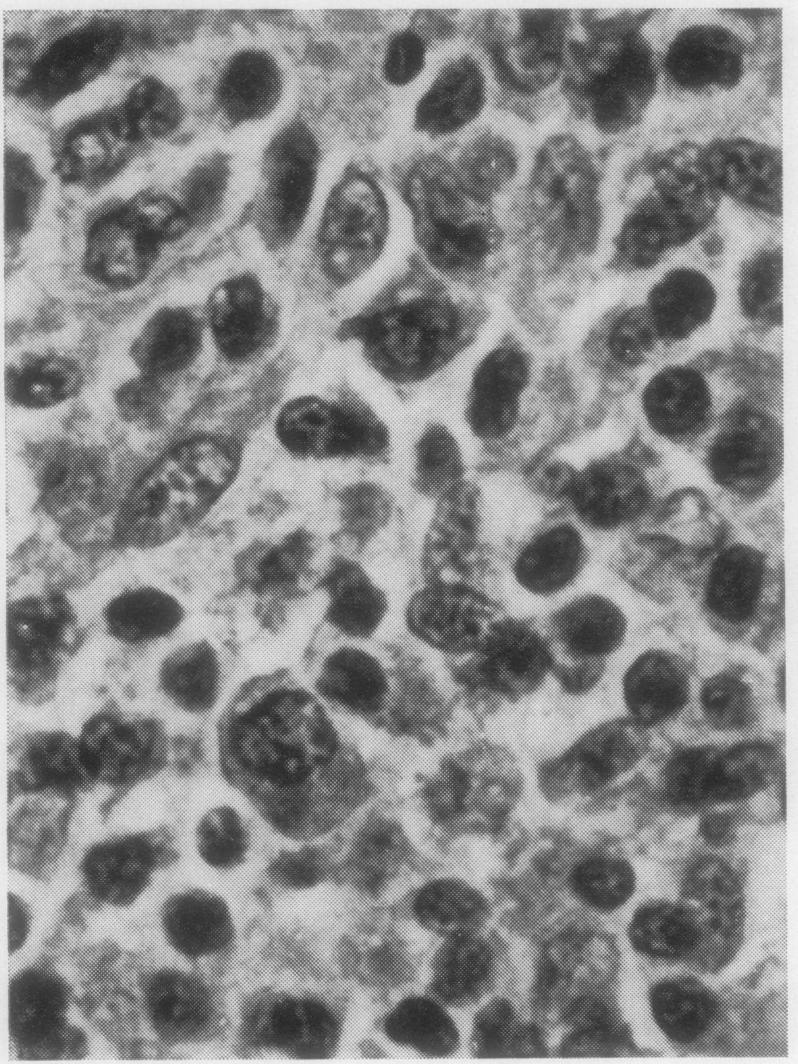

The histopathological appearances of the thymus, lymph nodes, spleen, and gut-associated lymphoid tissue (tonsil, Peyer's patches, and appendix) in cases of the combined immunity-deficiency syndrome are presented. The appearance of tissues remaining after foetal thymic transplants and the effects of such transplants on the morphology of lymph nodes are also discussed. Although thymic appearances are remarkably constant the picture in the lymph nodes and spleen may vary considerably. The tonsils, Peyer's patches, and appendix appear to constitute one lymphoid organ in man, at least with regard to the developmental arrest that may occur in this syndrome.

本文呈现了联合免疫缺陷综合征病例中胸腺、淋巴结、脾脏及肠道相关淋巴组织(扁桃体、派伊尔结和阑尾)的组织病理学表现。还讨论了胎儿胸腺移植后剩余组织的外观以及此类移植对淋巴结形态的影响。尽管胸腺的表现非常一致,但淋巴结和脾脏的情况可能有很大差异。扁桃体、派伊尔结和阑尾在人类中似乎构成一个淋巴器官,至少就该综合征可能出现的发育停滞而言是这样。